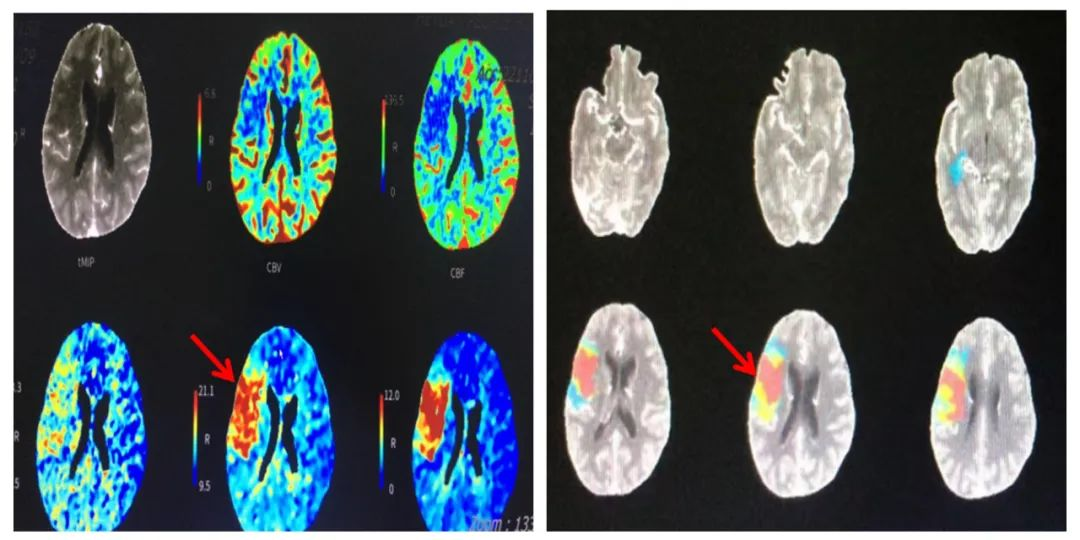

注:术前CTP提示全脑核心梗死面积为8.7ml,Mismatch面积为36.4ml,低灌注区体积为45.2ml,Mismatch比值为5.2。

患者为47岁女性,因“认知功能下降伴言语不清3小时余”来我院急诊求治,卒中团队考虑患者急性脑梗死予以静脉溶栓,进一步联合影像科团队通过CTP灌注明确患者存在右侧大脑中动脉M2段上干远端闭塞并存在明显缺血半暗带。神经内科钟小劲主任医师、何伟亮副主任医师、朱敏真副主任医师和温样春主治医师仔细研究判读患者术前大脑灌注图像,认为患者仍存在明显脑组织挽救空间,若不进行处理,会遗留明显的神经系统后遗症,经快速细致讨论确定方案并取得患者家属同意后,患者于急诊行“经皮颅内动脉取栓术”,成功开通了闭塞血管,效果显著,患者恢复良好,未遗留明显高级神经智能活动障碍,术后获得了患者和家属的一致认可。

神经内科介入团队